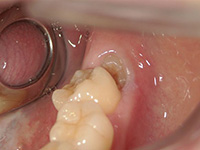

水平に埋まっている親知らずの抜歯の症例

水平に埋まった親知らずの抜歯は、頻度が高い手術です。

左下の親知らずが、水平に埋まっています。

歯ぐきを切開し、親知らずの一部を削りました。